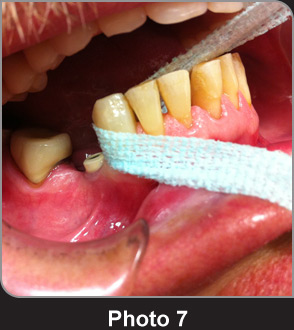

清潔牙齒43,44牙位將用于種植牙。

清潔34牙周圍。